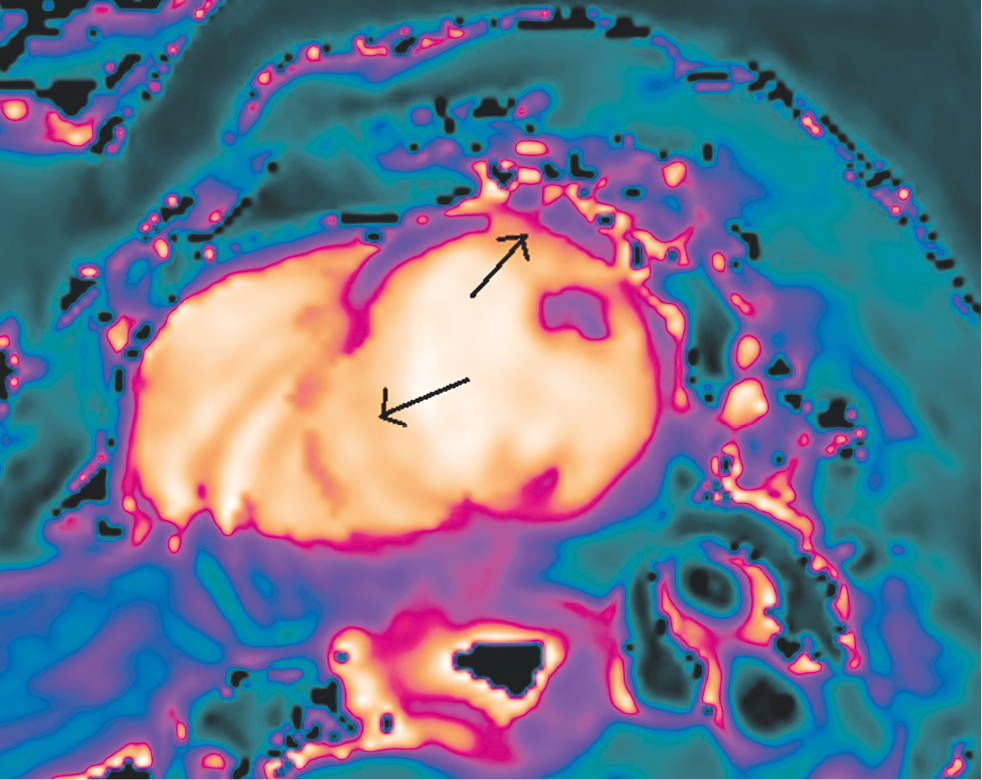

When analyzing the qualitative and quantitative indicators of native T1 mapping (modified Look–Locker inversion recovery), areas where the T1 relaxation time of the myocardium of the interventricular septum and anterior and lateral walls of the LV was increased were identified, which were more pronounced at the level of the apical and middle segments (Fig. 3). In a quantitative analysis, the relaxation time in the indicated areas was > 1200 ms (above the average norm for 3.0 T tomographs of 1122 ± 57 ms) [4]. Taking into account previous radiation therapy for left breast cancer, these areas are manifestations of diffuse myocardial fibrosis.

Fig. 3. Cardiac MRI, T1-mapping short axis of the left ventricle. The arrows indicate areas with increased T1-relaxation time localized in the interventricular septum and in the anterior wall of the left ventricle at the level of the apical segments

Рис. 3. Магнитно-резонансная томография сердца, Т1-картирование миокарда по короткой оси левого желудочка. Стрелки указывают области с повышенным временем Т1-релаксации, локализованные в межжелудочковой перегородке и в передней стенке левого желудочка на уровне начала срединных сегментов